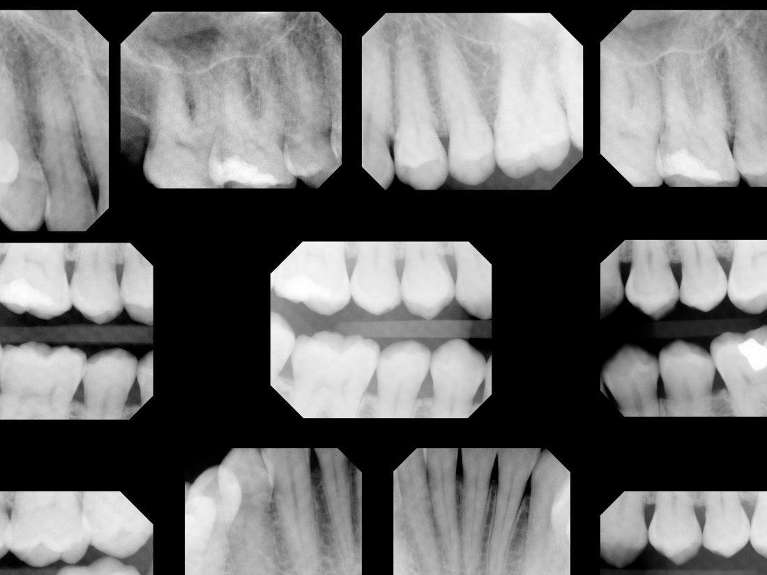

Digital X-Rays

Modern digital dental x-rays benefit patients in a number of ways:

• Digital x-rays expose patients to considerably less radiation than conventional film x-rays.

• Digital x-rays require almost no time for development, reducing time spent waiting in the dental chair.

• Digital x-rays allow for incredibly precise and accurate images for timely diagnoses.

• Digital x-rays are securely stored in your digital file and can be securely sent to your insurance company or specialists, when necessary.

Because no chemicals are needed for developing and no space is needed for film storage, digital x-rays are better for the environment.